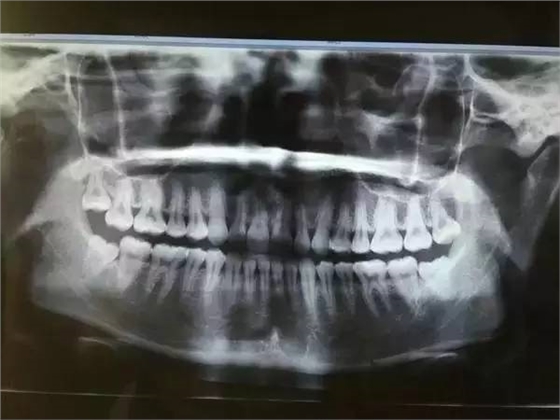

一般患者不自知,而由牙醫(yī)以X光確診得知。一般智齒萌生的空間缺乏,而會(huì)倒在第二大臼齒上,因而形成第二大臼齒清洗不易,乃至是牙齒部分吸收的表象,形成患者不舒服或牙疼。